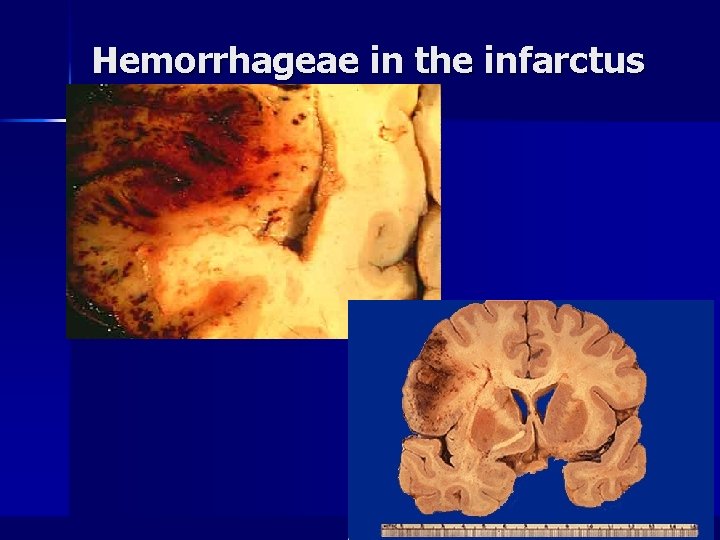

Hemorrhageae in the infarctus area